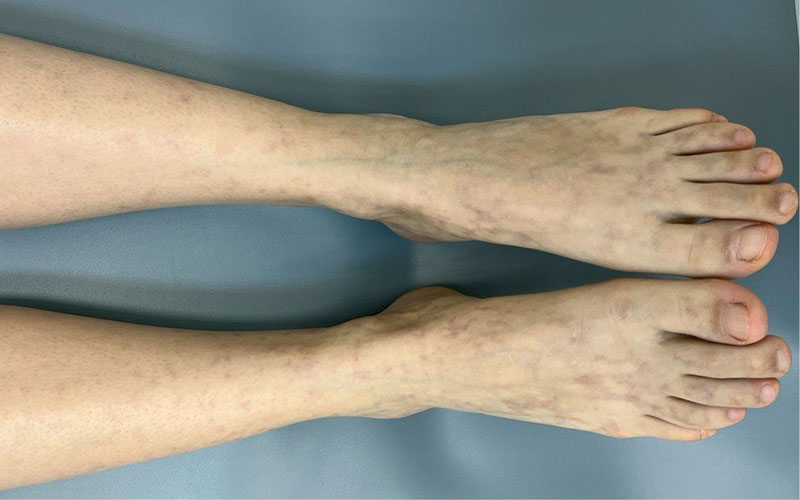

Рис. 1. Пациентка 34 лет с ЛВ и характерными сосудистыми пятнами

Под наблюдением находились 22 пациента женского и мужского пола (18 женщин и четверо мужчин) с диагнозом ливедоидной васкулопатии в возрасте от 34 до 78 лет. При поступлении в стационар кожный процесс у всех пациентов был локализован в области нижних конечностей и представлен пятнами синюшной окраски (рис. 1), различных очертаний и размеров, образующими петлистую сеть, или сочетанием синюшных пятен и мелких язвенных дефектов кожи в области лодыжек и тыла стоп, после заживления которых оставались белесоватые рубцы с зоной гиперпигментации вокруг. Субъективно пациентов беспокоили зябкость, тянущая боль в конечностях, пульсирующая боль в язвах.